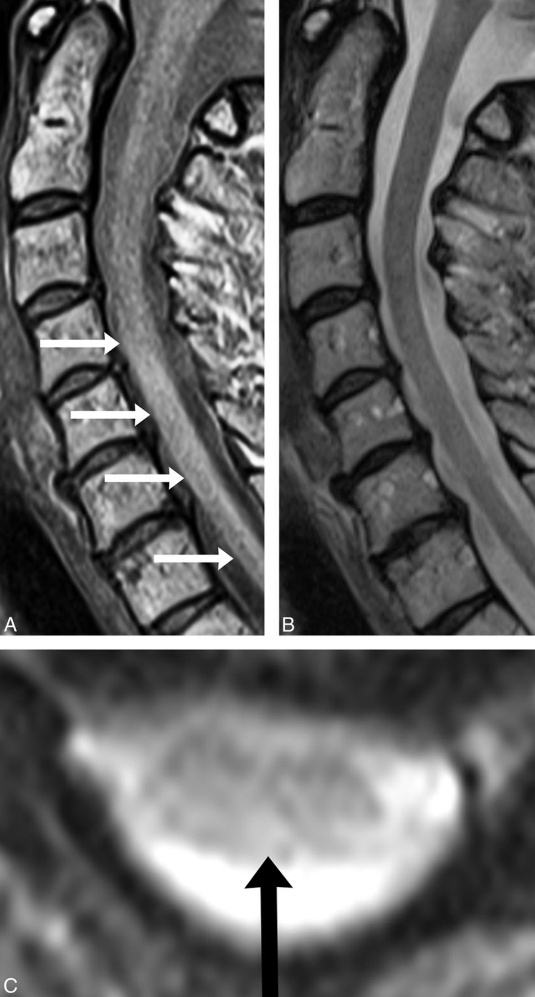

The Role of Flexion/Extension MRI

Flexion/extension MRI evaluates the spine in different positions—typically bending forward (flexion) and backward (extension). This allows doctors to assess how spinal segments behave under movement.

Flexion/extension MRI can reveal:

- Abnormal joint translation

- Excessive motion between vertebrae

- Segmental instability that is not visible in neutral imaging

- Dynamic stress on the spinal cord or nerve roots

For patients injured in car accidents, this type of imaging is especially valuable because ligament injuries often allow too much motion, not too little.

This is where proton density (PD) MRI sequences become important.

Why Proton Density (PD) MRI Matters

Proton density MRI is optimized to highlight soft tissue contrast, making it particularly useful for evaluating ligaments and joint capsules.

Upper cervical PD imaging can help identify:

- Ligament thickening or disruption

- Signal changes suggesting sprain or tearing

- Asymmetry between stabilizing structures

- Inflammatory changes related to trauma